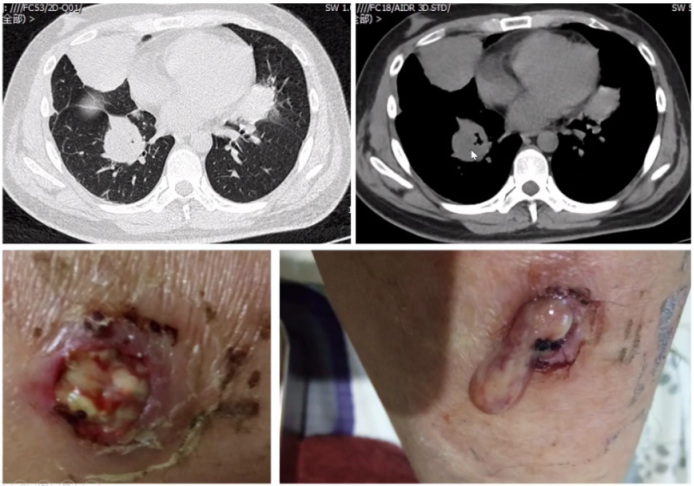

下图为青年男性患者,主诉间断咳嗽、发热伴双下肢破溃3个月。胸部CT可见肺内大片实性团块影,部分有空洞形成,内有液化坏死表现。下肢皮肤破溃,有脓性分泌物。肺活检和皮肤活检均提示为肉芽肿性血管炎(GPA)。病原学检查均为阴性。因此,该患者是血管炎性损伤所致病变。

图片